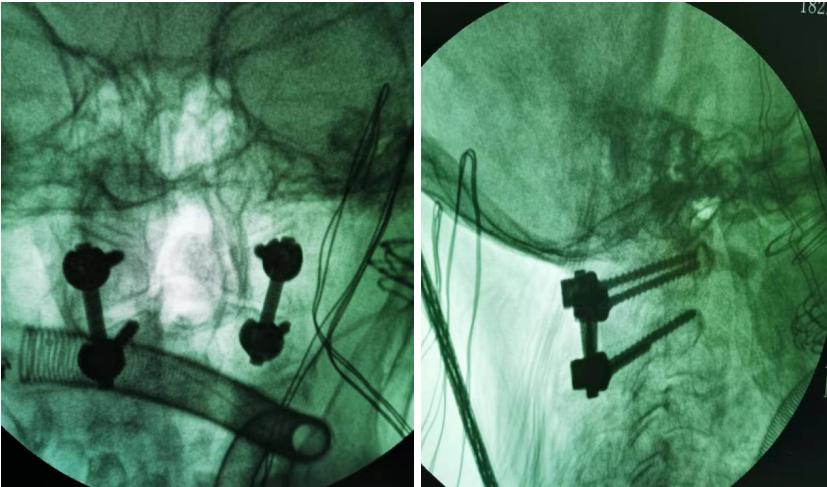

庆幸的是,面对患者及家属的信任和期待,南江县人民医院骨科医师团队在做好充分的术前准备后于12月8日成功为患者实施了手术。术后,许奶奶的寰枢椎脱位完美复位,疼痛及肢体麻木等症状都得到明显缓解,目前,许奶奶病情平稳,已经能佩戴头颈支具下地行走,日常生活能力也在进一步康复中。“如果不是南江县人民医院,如果不是张医生,我母亲可能会卧床一辈子了”,许奶奶的女儿激动地说。

图为术中透视影像